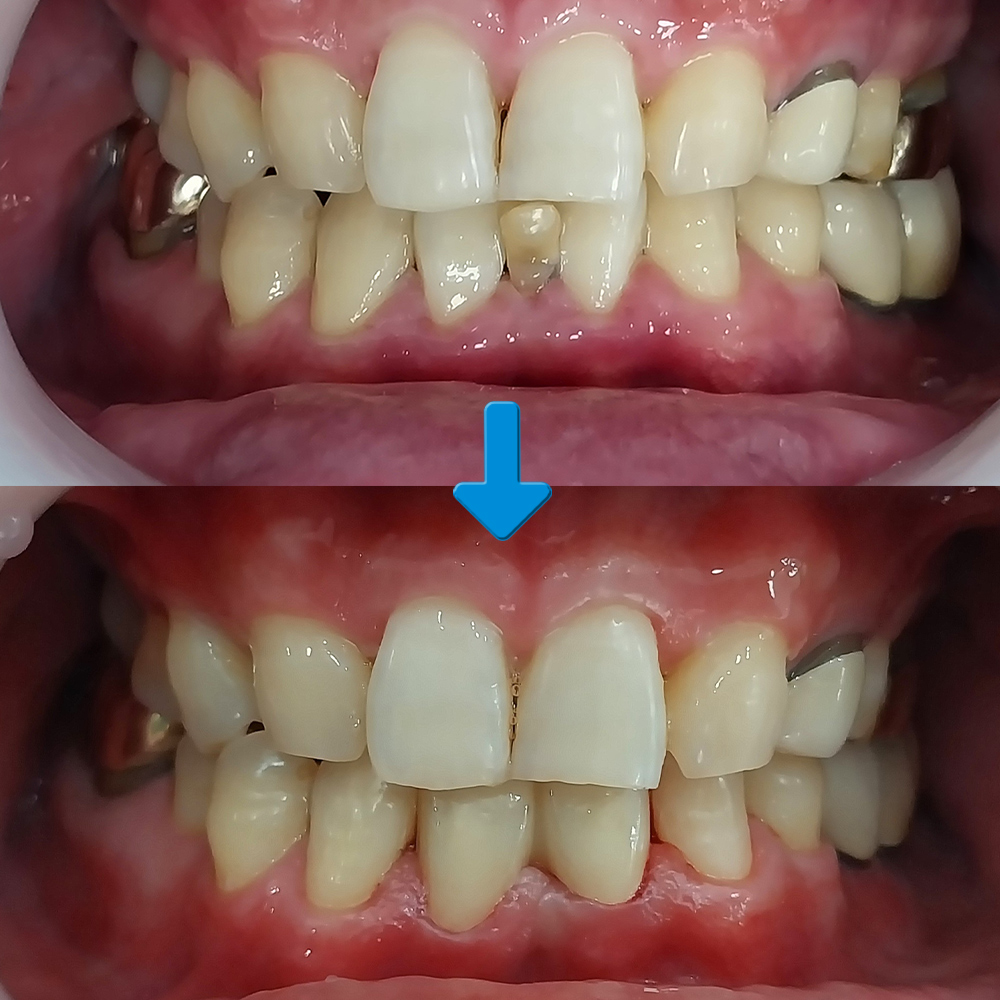

오늘은 가정동치과에서 아래쪽에 남아 있는 유치를 발치하고 브릿지를 진행하신 환자분을 소개해 드리도록 하겠습니다.

환자분께서는 아래 앞니에 유치가 빠지지 않고 남아 있어 보기 싫은데 뽑고 나서의 치료 방법 상담을 위해 내원해 주셨는데요. 다른 치아들은 모두 정상적으로 영구치 상태였지만 아래 앞니만 1개의 영구치가 결손되어 유치가 남아 있는 상황으로 발치 후 양옆의 치아와 조화로울 수 있도록 브릿지를 계획하게 되었습니다.

앞니 브릿지 수복을 통해 기능과 심미성을 동시에 회복할 수 있게 되었습니다.

치아가 없는 부위는 보철물이 잇몸 위에 놓이게 되기 때문에 치료기간이 1~2주 정도 소요되며, 치료 비용도 임플란트에 비해 저렴해 가격부담이 적어 빠르게 회복이 가능하였습니다. 가정동치과의 앞니 치료는 보철물의 크기, 색상, 모양, 각도, 좌우대칭이 조화되어야 하기 때문에 까다롭고 어려운 치료에 속하며 임플란트로 치료한 앞니는 부조화 가능성이 있는 반면 브릿지는 자연스럽고 치아의 형태도 반듯해 정돈된 인상을 줄 수 있다는 장점으로 많은 분들이 선택하고 계십니다.